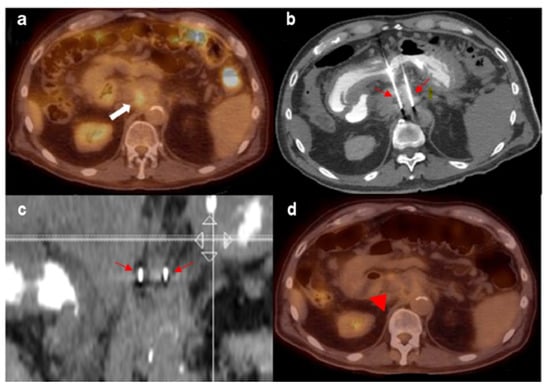

Figure 2 demonstrates a case example using IRE to treat unresectable LAPC. A 72-year-old man, initially diagnosed with pancreatic adenocarcinoma in 2014, underwent chemotherapy and IRE in 2014, and had external radiation to the neck of the pancreas. Follow-up PET/CT 5 years later demonstrated FDG uptake within an ill-defined soft tissue density inseparable from the pancreatic head at the level of the celiac trunk, concerning for tumor recurrence. Patient also had elevated CA-19–9 levels. Repeat IRE treatment was performed with two probes, with no residual FDG uptake in the post-treatment PET.

Figure 2. (a) FDG-avid recurrent pancreatic mass (white thick arrow). (b,c) Two IRE probes in place bracketing the mass (thin red arrows). (d) No residual FDG avidity post-treatment (red arrow).